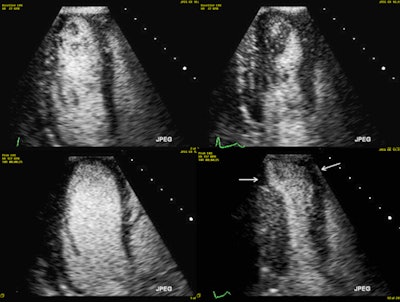

They used the Bruce treadmill exercise protocol for the exercise stress echo, aiming to reach the maximum predicted heart rate. Standard images were acquired at rest and immediately after peak exercise. For the dobutamine stress echo, they used the standard 3 min stages protocol with incremental dobutamine doses of 5, 10, 20, 30 and 40 µg/kg/min. Ultrasound contrast was administered if at least two myocardial segments weren't seen on baseline echo images.

In all, 210 of 257 (81.7%) of the high-pretest probability patients had dobutamine stress echo, while 18.3% had an exercise stress echo. All tests reached high heart rates, and the researchers found no adverse events, though two patients had hypotension at the peak of dobutamine stress, and one developed atrial fibrillation.

A total of 106 patients (41.2%) had a positive stress echo, and 61 underwent invasive angiography, in which 15 (24.6%) were revascularized. The average cost per patient for all studies was 654 pounds (748 euros). If NICE guidance had been followed, the costs would have been significantly higher at 1,400 pounds (1,602 euros), a difference of 746 pounds (853 euros).